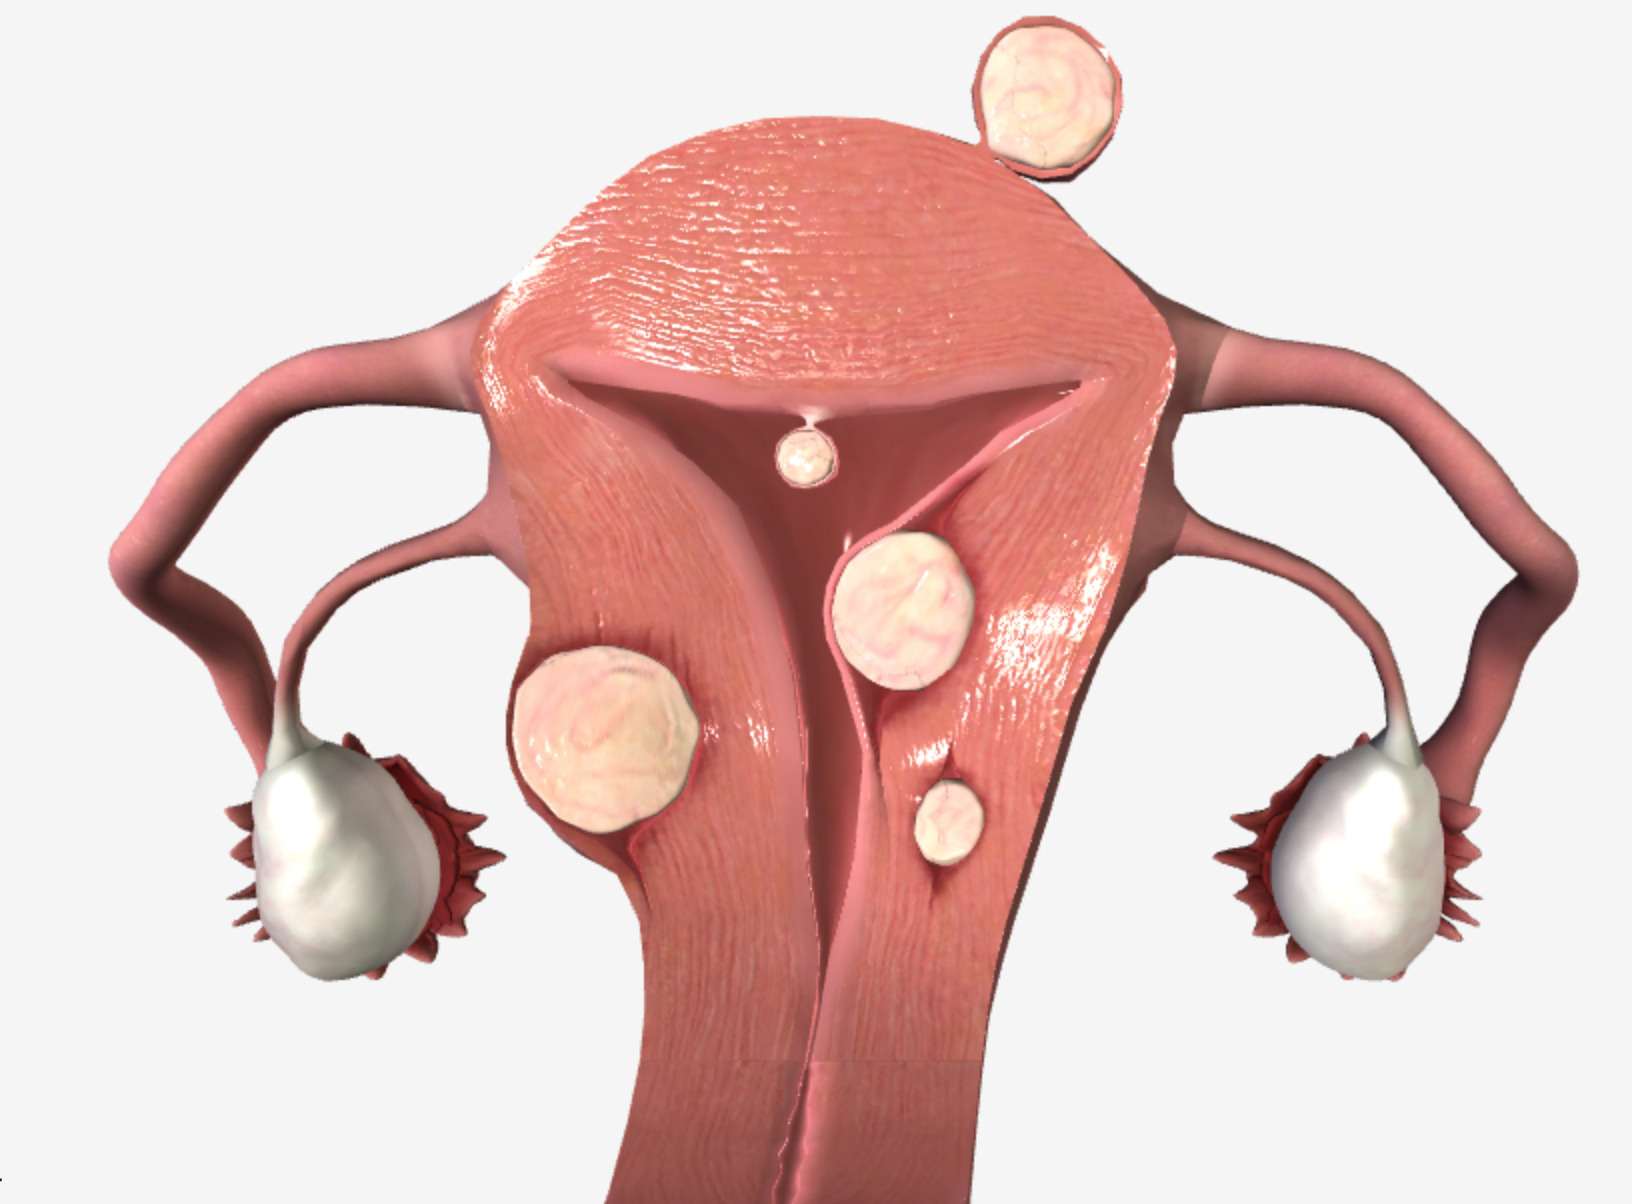

leiomyoma fibroid uterine uterus types fibroids ppt location primary three there leiomyomas powerpoint presentation multiple classified primarily according most slideserve

leiomyoma uterus causes uterine fibroid leiomyomas osmosis malignant transformation

uterine fibroids bleeding leiomyoma leiomyosarcoma fibroid abnormal endometrial intramural submucosal subserosal pedunculated malignancy cervical hyperplasia sarcomas lecturio

leiomyomas uterine clinical review location radiology key